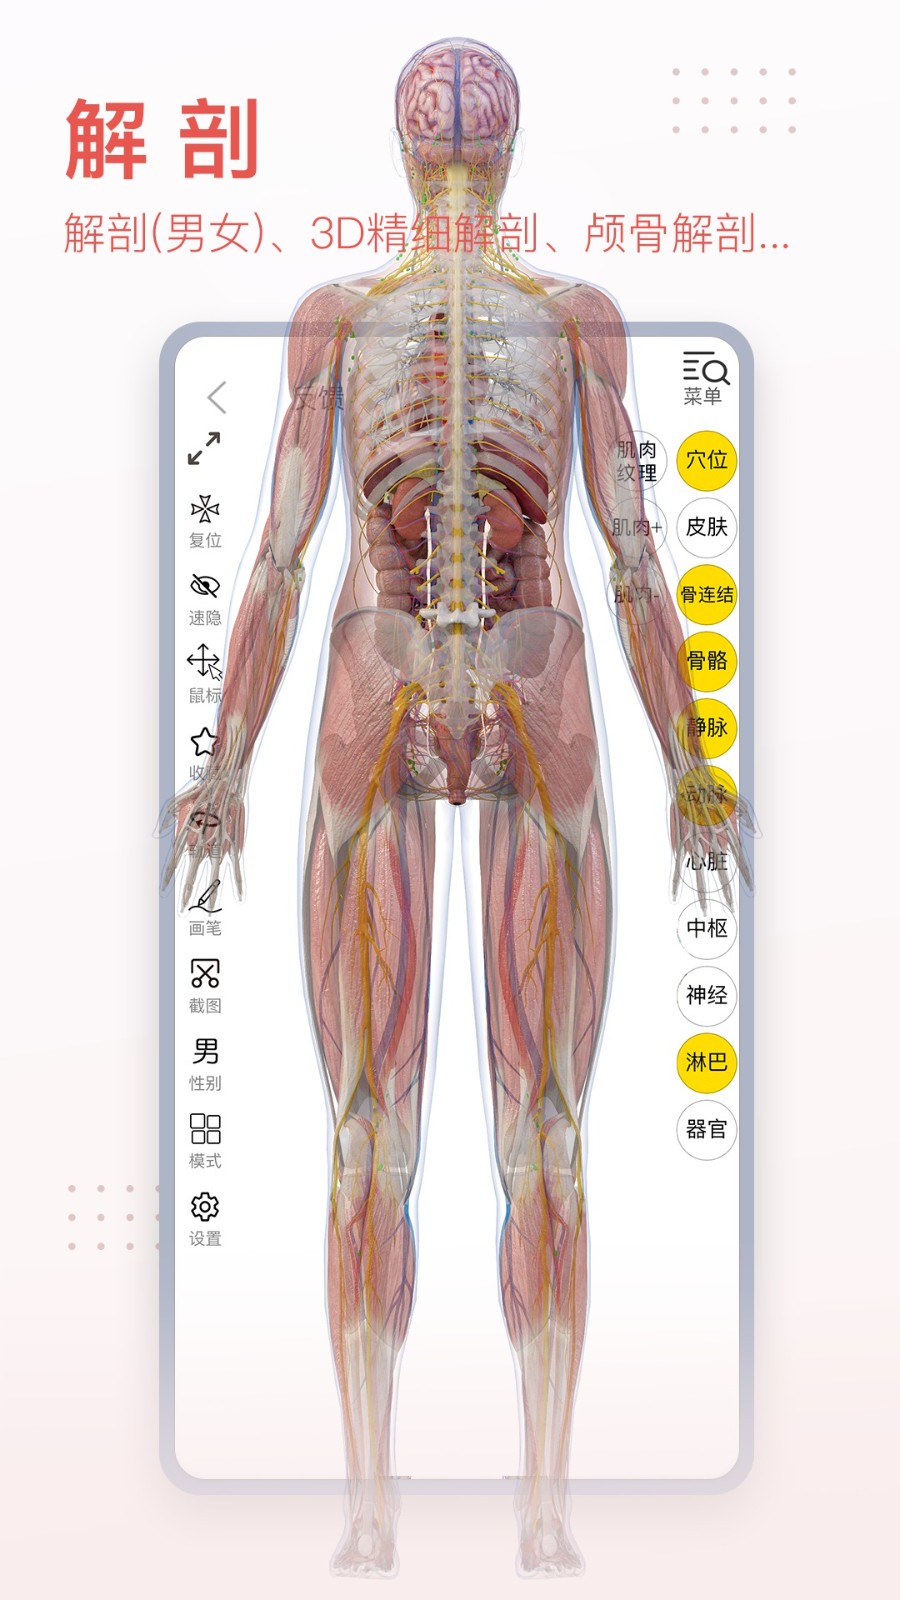

3dbody系统解剖手机版是专为医学行业打造的掌上人体解剖学习软件,详细的三维解刨图片,解释详尽。3DBody系统解剖手机版是系统模块,相较于局部模块版,解剖更加的详细,需要的赶紧下载吧。

3Dbody系统解剖提供了男体一套全三维的数字模型,2000多个人体结构,涵盖了人体所有解剖系统。

3DBody作为集大成者,不仅数据详实,而且操作功能强大,国内外高度领先,通过本软件实时三维操作,轻易获得层层解剖人体的机会。作为内容最全面的3D解剖app,电脑版本已经被证实为最受欢迎的医学软件之一。

软件包括人体十二大系统的3D解剖.经络穴位和反射区,同时提供大量肌骨康复动画,全部三维体验,界面精美,内容专业,操作体验佳。

生殖系统 Reproductive system

泌尿系统 Urinary system

呼吸系统 Respiratory system

循环系统 Circulatory system

消化系统 Digestive system

内分泌系统 Endocrine system

皮肤系统 Integumentary system

淋巴系统 Lymphatic system

肌肉系统 Muscular system

神经系统 Nervous system

骨骼系统 Skeletal system